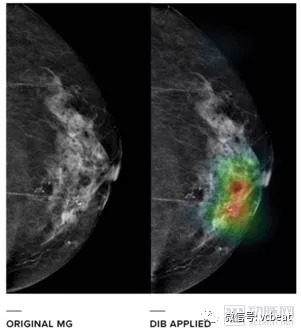

使用BID算法前后对比(乳房X光摄影术)

DIB用于乳房X光摄影术的目的是提高乳腺癌的检出率,降低误诊率:

1)检测和定位病变;

2)为患者的乳腺影像报告和数据系统提供建议;

3)预测病变为恶性的概率。